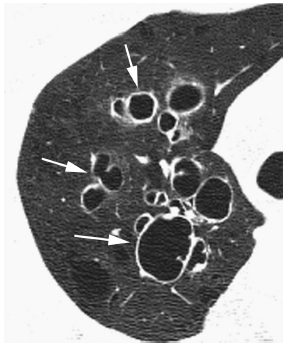

支气管扩张的CT表现是什么样的

CT 区分支气管扩张的原因_CT_支气管扩张